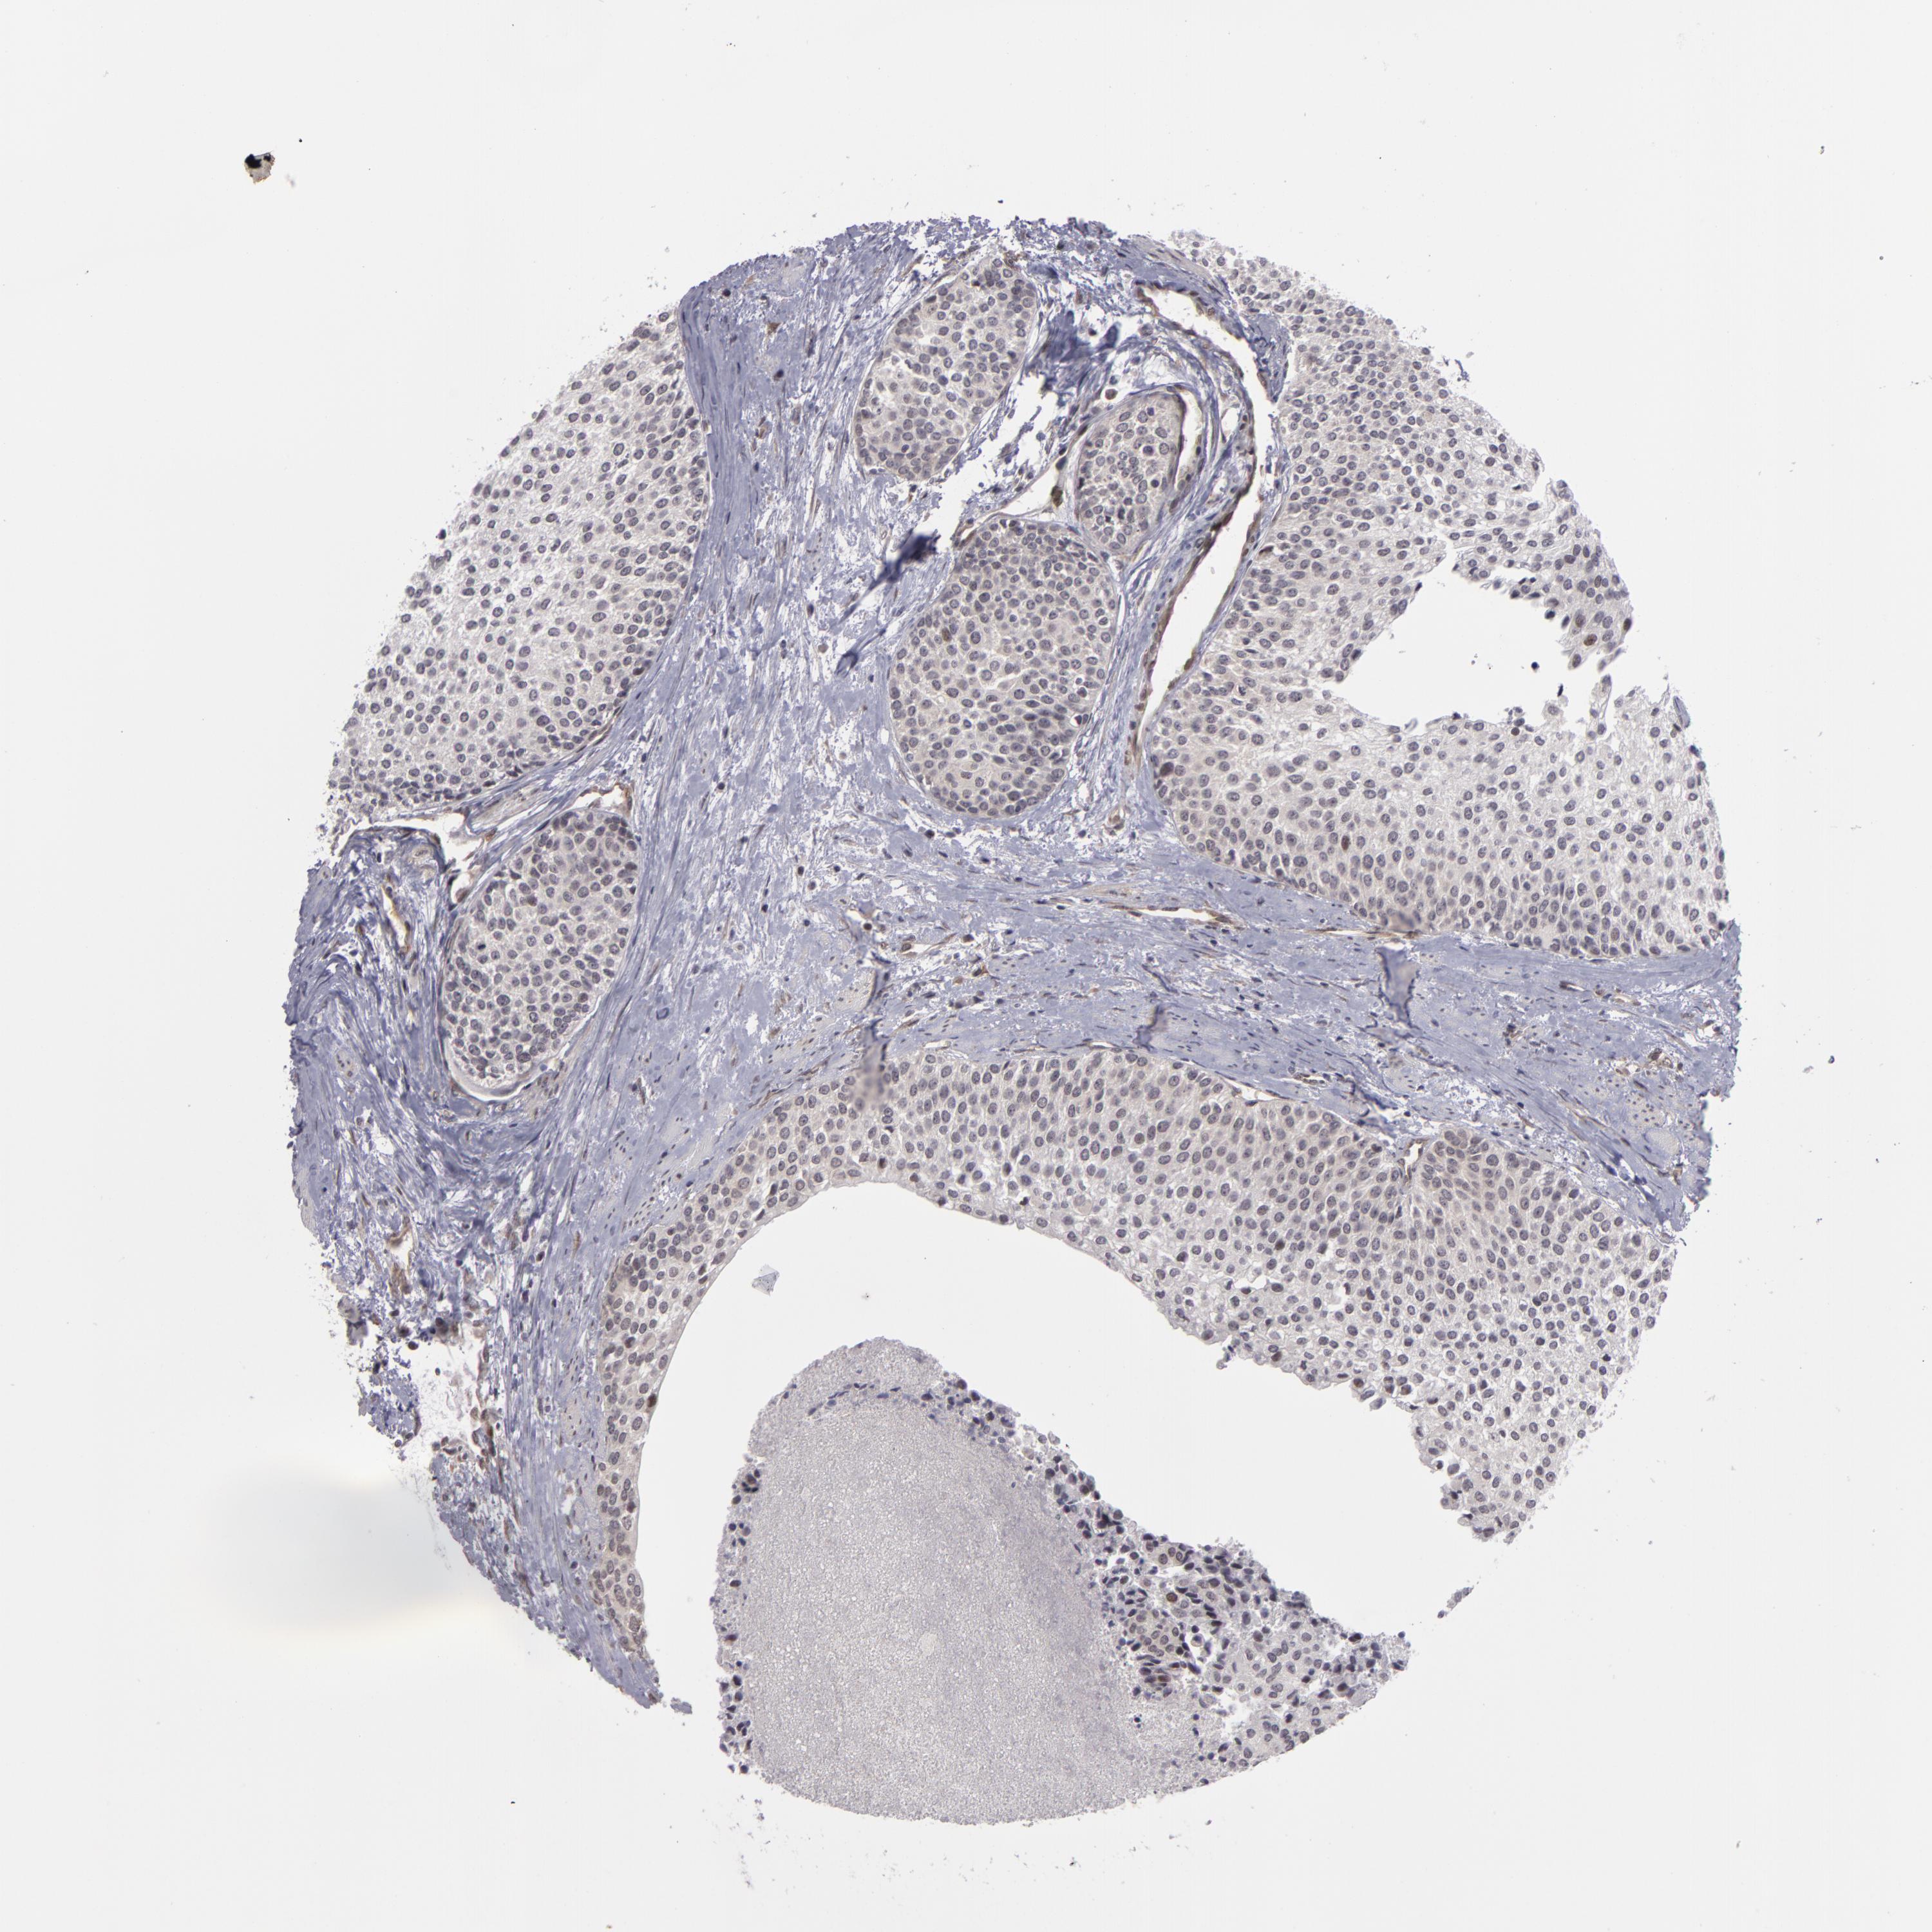

UROTHELIAL CANCER - Protein expressioni

A mouse-over function shows sample information and annotation data. Click on an image to view it in a full screen mode. Samples can be filtered based on level of antibody staining by selecting one or several of the following categories: high, medium, low and not detected. The assay and annotation is described here.

Note that samples used for immunohistochemistry by the Human Protein Atlas do not correspond to samples in the TCGA dataset.

Antibody stainingi

Antibody staining in the annotated cell types in the current human tissue is reported as not detected, low, medium, or high, based on conventional immunohistochemistry profiling in selected tissues. This score is based on the combination of the staining intensity and fraction of stained cells.

Each image is clickable and will lead to virtual microscopy that enables deeper exploration of all samples and also displays staining intensity scores, fraction scores and subcellular localization as well as patient and tissue information for each sample.

Antibody HPA001493

Staining

High

Medium

Low

Not detected

Intensity

Strong

Moderate

Weak

Negative

Quantity

>75%

75%-25%

<25%

None

Location

Nuclear

Cytoplasmic/membranous

Cytoplasmic/membranous,nuclear

Urothelial carcinoma, High grade